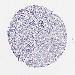

LIVER CANCER - Protein expressioni

A mouse-over function shows sample information and annotation data. Click on an image to view it in a full screen mode. Samples can be filtered based on level of antibody staining by selecting one or several of the following categories: high, medium, low and not detected. The assay and annotation is described here.

Note that samples used for immunohistochemistry by the Human Protein Atlas do not correspond to samples in the TCGA dataset.

Antibody stainingi

Antibody staining in the annotated cell types in the current human tissue is reported as not detected, low, medium, or high, based on conventional immunohistochemistry profiling in selected tissues. This score is based on the combination of the staining intensity and fraction of stained cells.

Each image is clickable and will lead to virtual microscopy that enables deeper exploration of all samples and also displays staining intensity scores, fraction scores and subcellular localization as well as patient and tissue information for each sample.

Antibody CAB002165

Staining

High

Medium

Low

Not detected

Intensity

Strong

Moderate

Weak

Negative

Quantity

>75%

75%-25%

<25%

None

Location

Nuclear

Cytoplasmic/membranous

Cytoplasmic/membranous,nuclear

Carcinoma, Hepatocellular, NOS

Cholangiocarcinoma